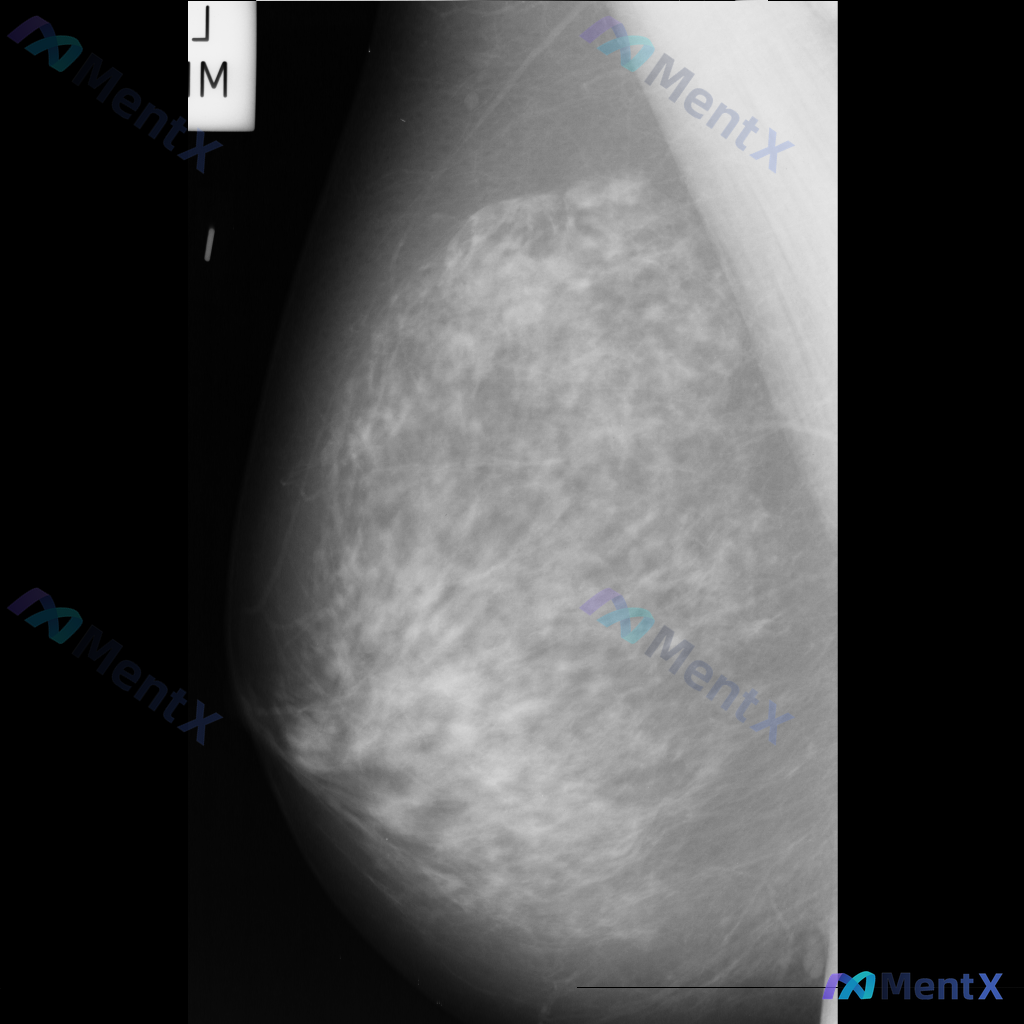

整理到一份右侧乳腺内外斜位钼靶X光片的影像资料,大家可以一起讨论下:

- 影像中可见散在的纤维腺体密度,密度较高

- 发现多发斑点状或细小钙化点,分布散在,目前倾向良性特征

- 另有局部模糊的不对称致密影,与背景腺体组织融合,未见明确毛刺或结构扭曲等恶性特征